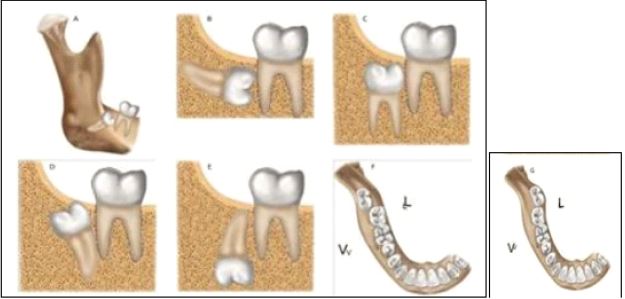

Winter's classification for lower third molars: A: mesioangular, B: horizontal, C: vertical, D: distoangular, E: inverted, F: vestibuloversion, G: linguoversion (15,16-17)

FIGURE 2

Elaborated by: the authors.